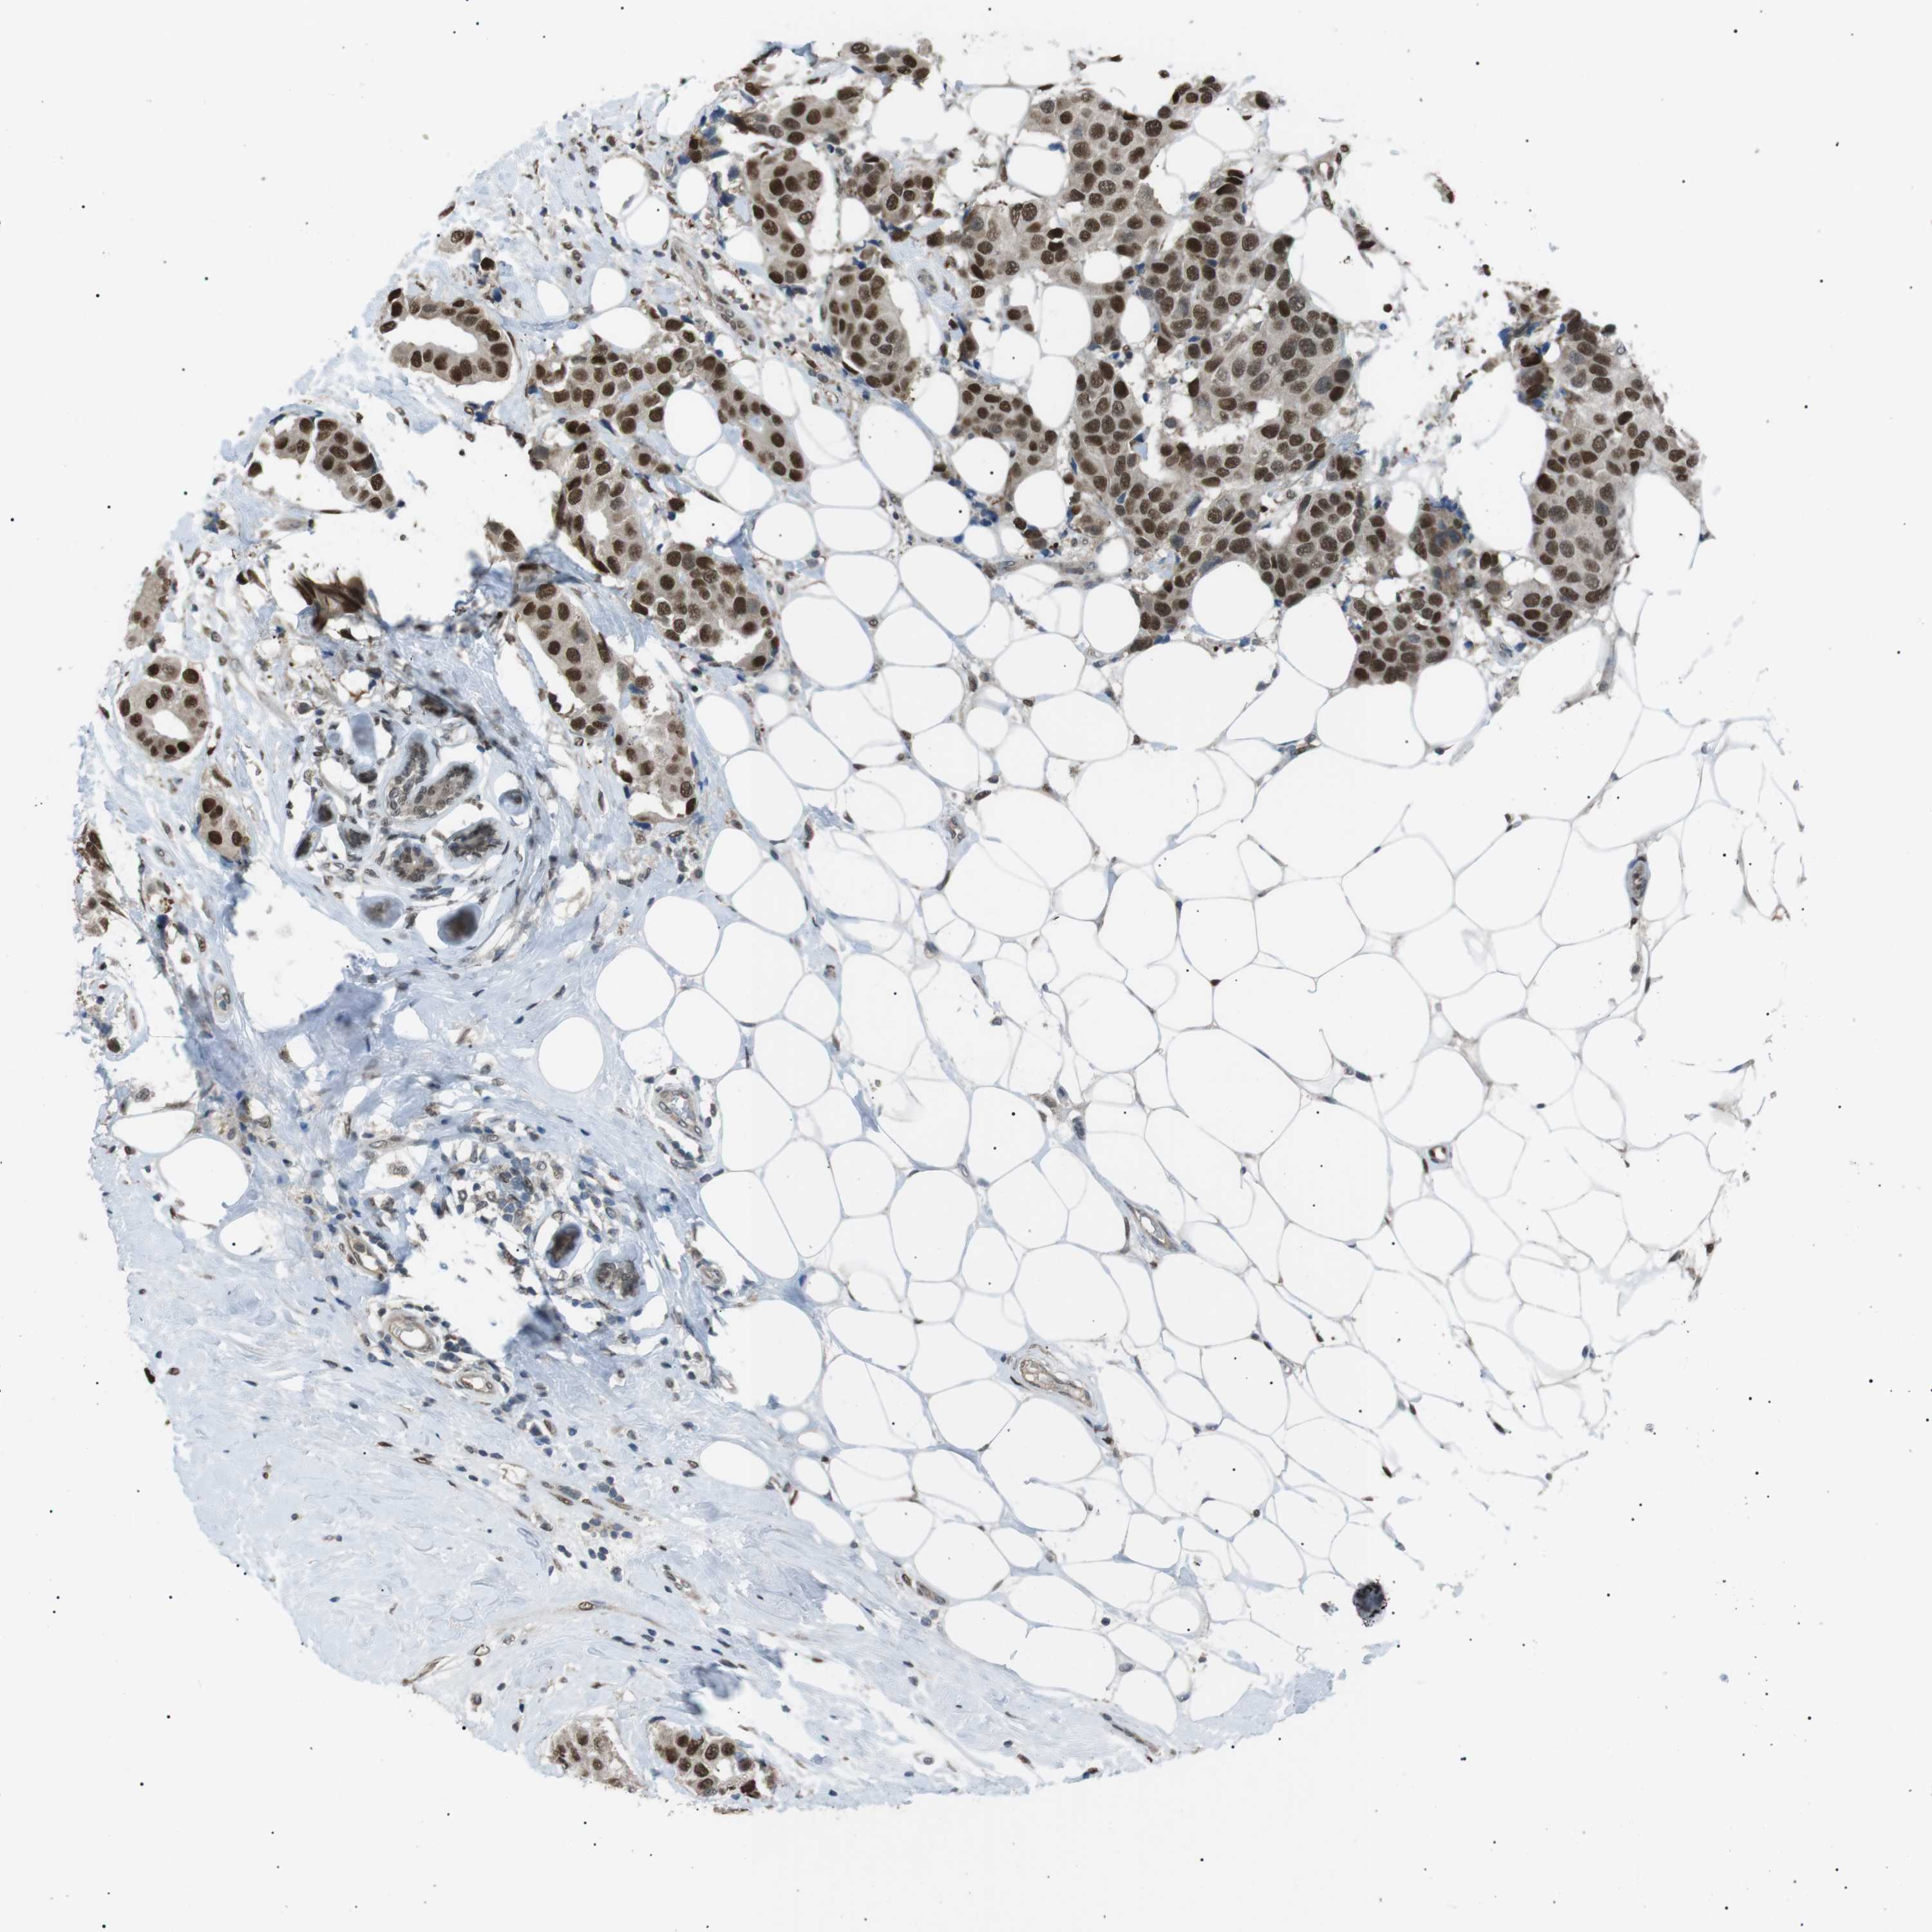

BRCA TCGA BRCA VALIDATION PROTEIN EXPRESSION